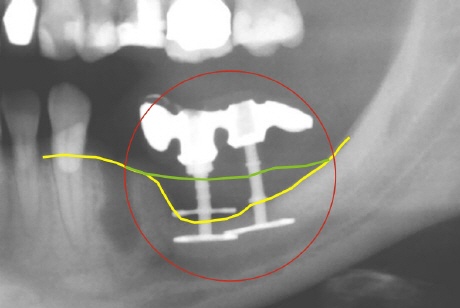

Knochenabbau

Die Röntgenaufnahme zeigt den massiven Knochenverlust an zwei Diskimplantaten (zwischen der grünen und der gelben Linie). Die gelbe Linie zeigt den aktuellen Knochenverlauf, die grüne demonstriert den ursprünglichen. Die obere Scheibe an dem linken Diskimplantat ist gar nicht mehr von Knochen umgeben. Die Implantate sollten entfernt werden, um weiteren Knochenabbau zu verhindern.